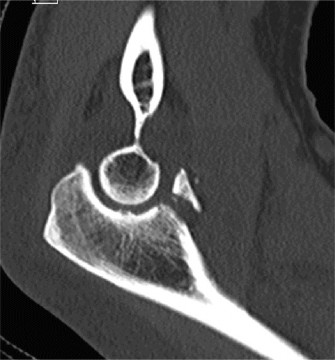

A radiograph of the patient is shown in Figure 2–68. Based on the information obtained thus far, what is the most likely classification of this injury?

🔍 Click to enlargeClinical Radiograph / Orthopedic Image

Figure 2–68

The correct answer is (D). Based on the amount of distance between the coracoid process and the clavicle (CC interspace); the fact that the distal clavicle is tenting the skin and that the joint is irreducible, this AC joint separation can best be classified as a type V. The remaining answer choices are incorrect based on the information provided in Table 2–10 describes the Rockwood classification of AC joint injuries.